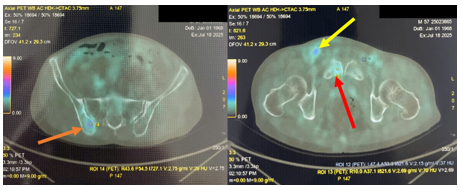

2. Hình ảnh tổn thương khuyết xương ở thân đốt sống L4, xương chậu phải, xương mu phải, tăng chuyển hóa FDG khả năng ác tính (SUVmax: 3.08).

Hình 4. Hình ảnh tổn thương xương chậu phải (mũi tên màu da cam), xương mu phải (mùi tên màu vàng), tăng chuyển hóa FDG khả năng ác tính (SUVmax: 3.08);hạch bẹn 2 bên tăng chuyển hóa FDG, với tổn thương có kích thước lớn và tăng bắt FDG rõ rệt ở hạch bẹn phải (mũi tên vàng), SUVmax: 4,66.